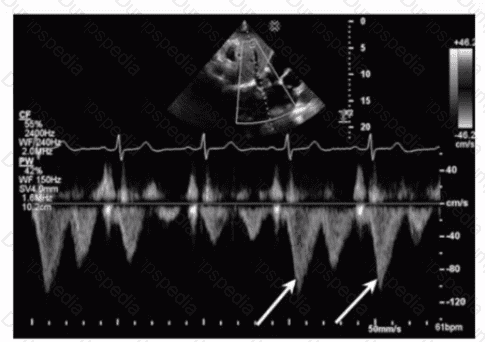

Which maneuver aids in uncovering potential diastolic dysfunction while performing pulsed wave Doppler of the mitral valve?

The variables necessary to calculate mitral regurgitant (MR) effective orifice area by the proximal isovelocity surface area (PISA) equation include MR aliasing hemispheric radius, the aliasing velocity, and which other parameter?